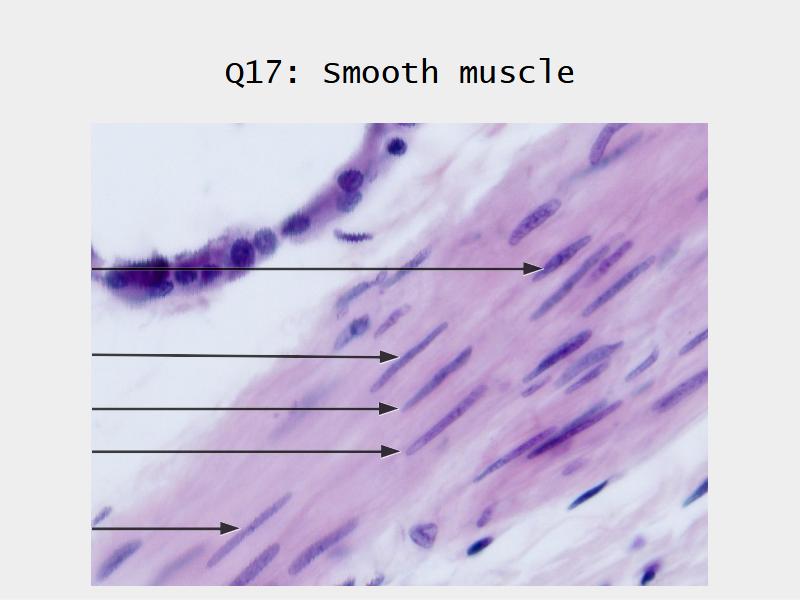

Name three types of contractile cells.